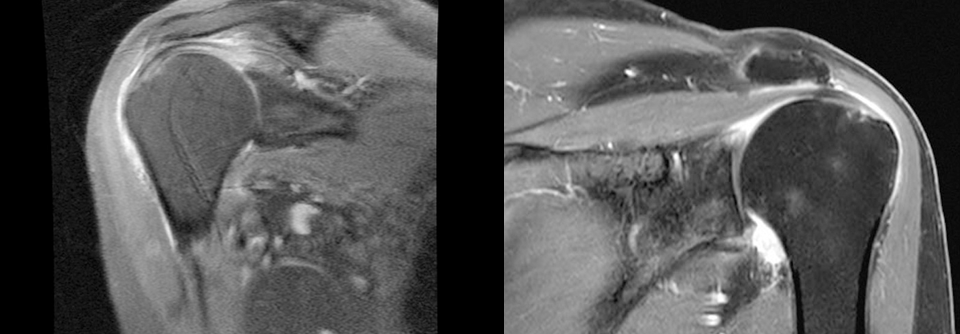

In vielen Empfehlungen zur Therapie der adhäsiven Kapsulitis rangieren intrartikuläre Steroidinjektionen auf den hinteren Plätzen. Einer aktuellen Metaanalyse zufolge ist das ein Fehler.

Eine intraartikuläre (i.a.) Injektion von Steroiden zeigt bei der frischeren adhäsiven Kapsulitis die besten Ergebnisse. Die Erfolgsaussichten steigen weiter, wenn Patienten zusätzlich Physiotherapie erhalten. Das Angebot an Behandlungsmöglichkeiten der Frozen Shoulder ist riesig, aber eine wirklich evidenzbasierte Strategie gibt es nicht.

Um die Effektivität der Maßnahmen besser einordnen zu können, werteten Forscher 65 Studien mit rund 4000 Patienten aus. Die meisten litten kürzer als ein Jahr unter der Schultersteife. Schmerz und Funktion waren die primären Endpunkte. Die i.a. Injektion von Steroiden zeigte für den Untersuchungszeitraum ≤ 12 Wochen als einzige Maßnahme eine statistische und klinische Überlegenheit gegenüber anderen Maßnahmen. Dieser Vorteil schien für etwa sechs Monate anzuhalten. Ein häusliches Trainingsprogramm mit einfachen Übungen, Dehnen und Physiotherapie steigerte die positiven Effekte im Zeitraum zwischen zwölf Wochen und einem Jahr.

Die Forscher raten dazu, Betroffenen die i.a. Injektion schon beim Erstkontakt anzubieten. Ob die Therapie auch bei einer Kapsulitisdauer von über einem Jahr noch so gut anschlägt, lässt sich aus den Daten nicht sicher ableiten. Erste Ergebnisse deuten aber auf einen Benefit hin.